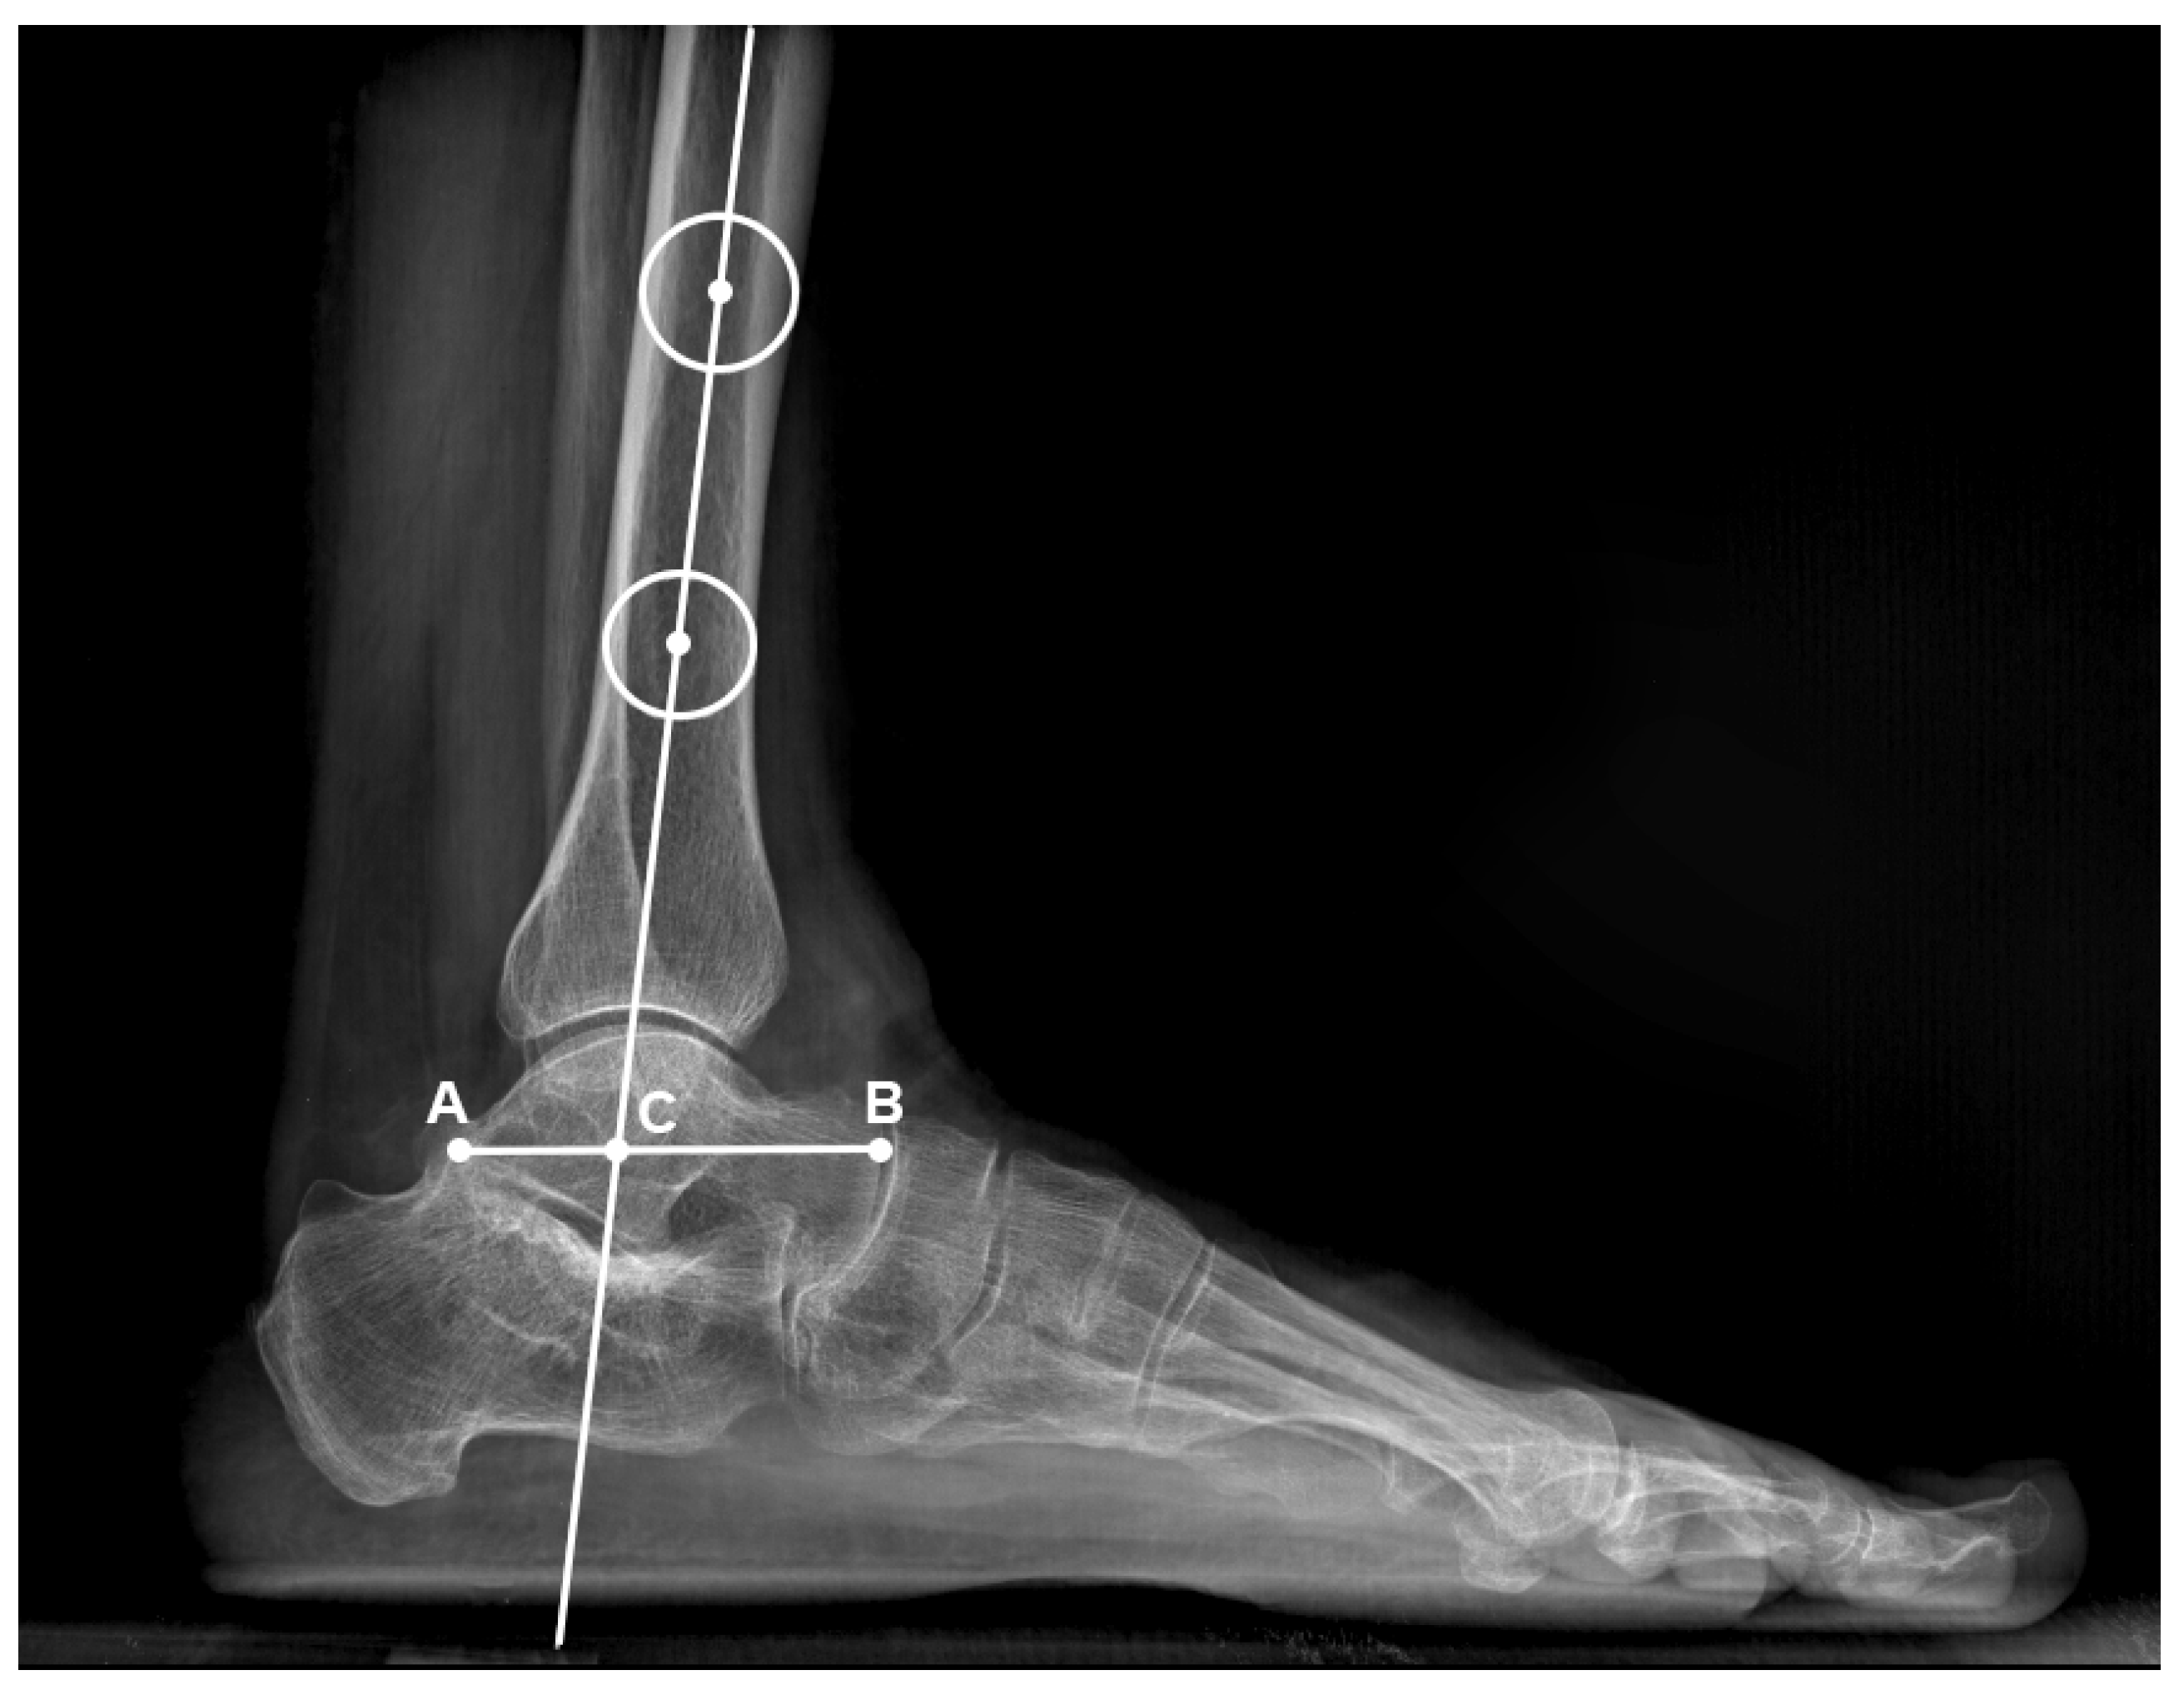

• The tibiotalar ratio (Figure 2): Defined as the ratio between the length of the talus segment posterior to the tibial axis and the overall longitudinal length of the talus in lateral view. The normal value is reported in the literature to be 33.4% ± 3.3% [16].

Figure 2. Tibiotalar ratio measurement, defined as the ratio between the length of the talus segment posterior to the tibial axis and the overall longitudinal length of the talus in lateral view. The tibiotalar ratio is defined as the ratio between the AC and AB.